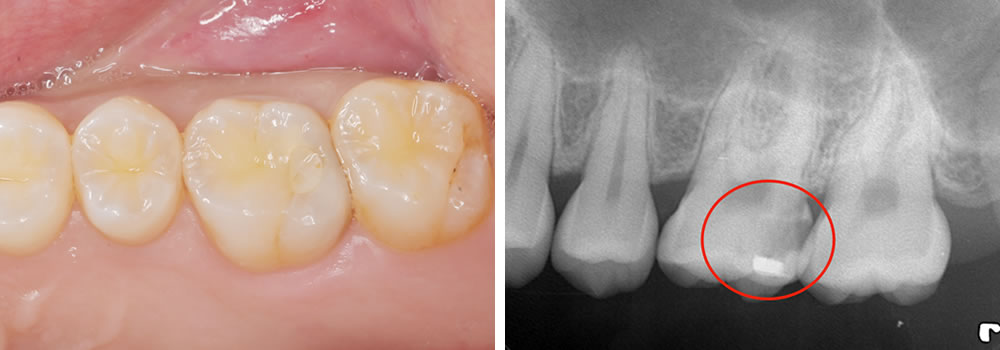

MTAセメントによる断髄処置により歯髄の温存を図った症例

MTAセメントによる断髄処置により歯髄の温存を図った症例 治療前の口腔内写真とレントゲンです。左上第一大臼歯に大きな虫歯が認められます。 今回はBioMTAセメントという材料を使用し、歯の神経を温存する治療を行っていきま […]